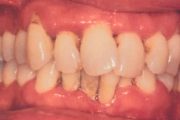

Krooniline parodontiit

Krooniline parodontiit on mikroobide poolt põhjustatud hammaste tugikudede põletik, mille tulemusena tekib progresseeruv alveolaarluu (nähtav röntgenograamil) ja periodontaalligamendi destruktsioon, igemetaskute moodustumine, igeme retsessioon või mõlemad kahjustused kombineeritult. Loe edasi »

- igemepiir on taandunud (3)

- igemed on tursunud/vohavad (17)

- igemed veritsevad (19)

- igemed punetavad (21)